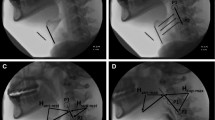

We defined sequential swallowing a priori as demonstrating two or more consecutive swallows where the HLC did not return to rest, and the pharynx lacked complete patency between swallows. This definition was derived based on the aforementioned compilation of potential HLC patterning characteristics found in the works of Chi-Fishman and Sonies [4, 15] and Daniels et al. [2, 5, 16]. In addition, these characteristics were appraised relative to distinguishing characteristics of discrete swallows [4] to generate a priori operational definitions for the HLC types used in our study (modelled after Daniels et al. [2, 5, 16]), which are detailed in Table 1 and captured in images (Figs. 1, 2, 3). HLC types were identified and coded according to the following characteristics: HLC movement, epiglottic position, and arytenoid-epiglottic closure integrity.

Hyolaryngeal complex (HLC) Type III. Yellow marker = Tracing of the hyoid/epiglottis. Blue arrow = Open laryngeal vestibule. Red arrow = Closed laryngeal vestibule. Green marker = Tracing of pharyngeal patency. A The rest position frame. B The frame of maximum pharyngeal patency between swallows (less patent than A). C The hyoid position frame during the end of the first swallow. D The HLC is slightly lower than C, sustained epiglottic inversion, and the laryngeal vestibule is open